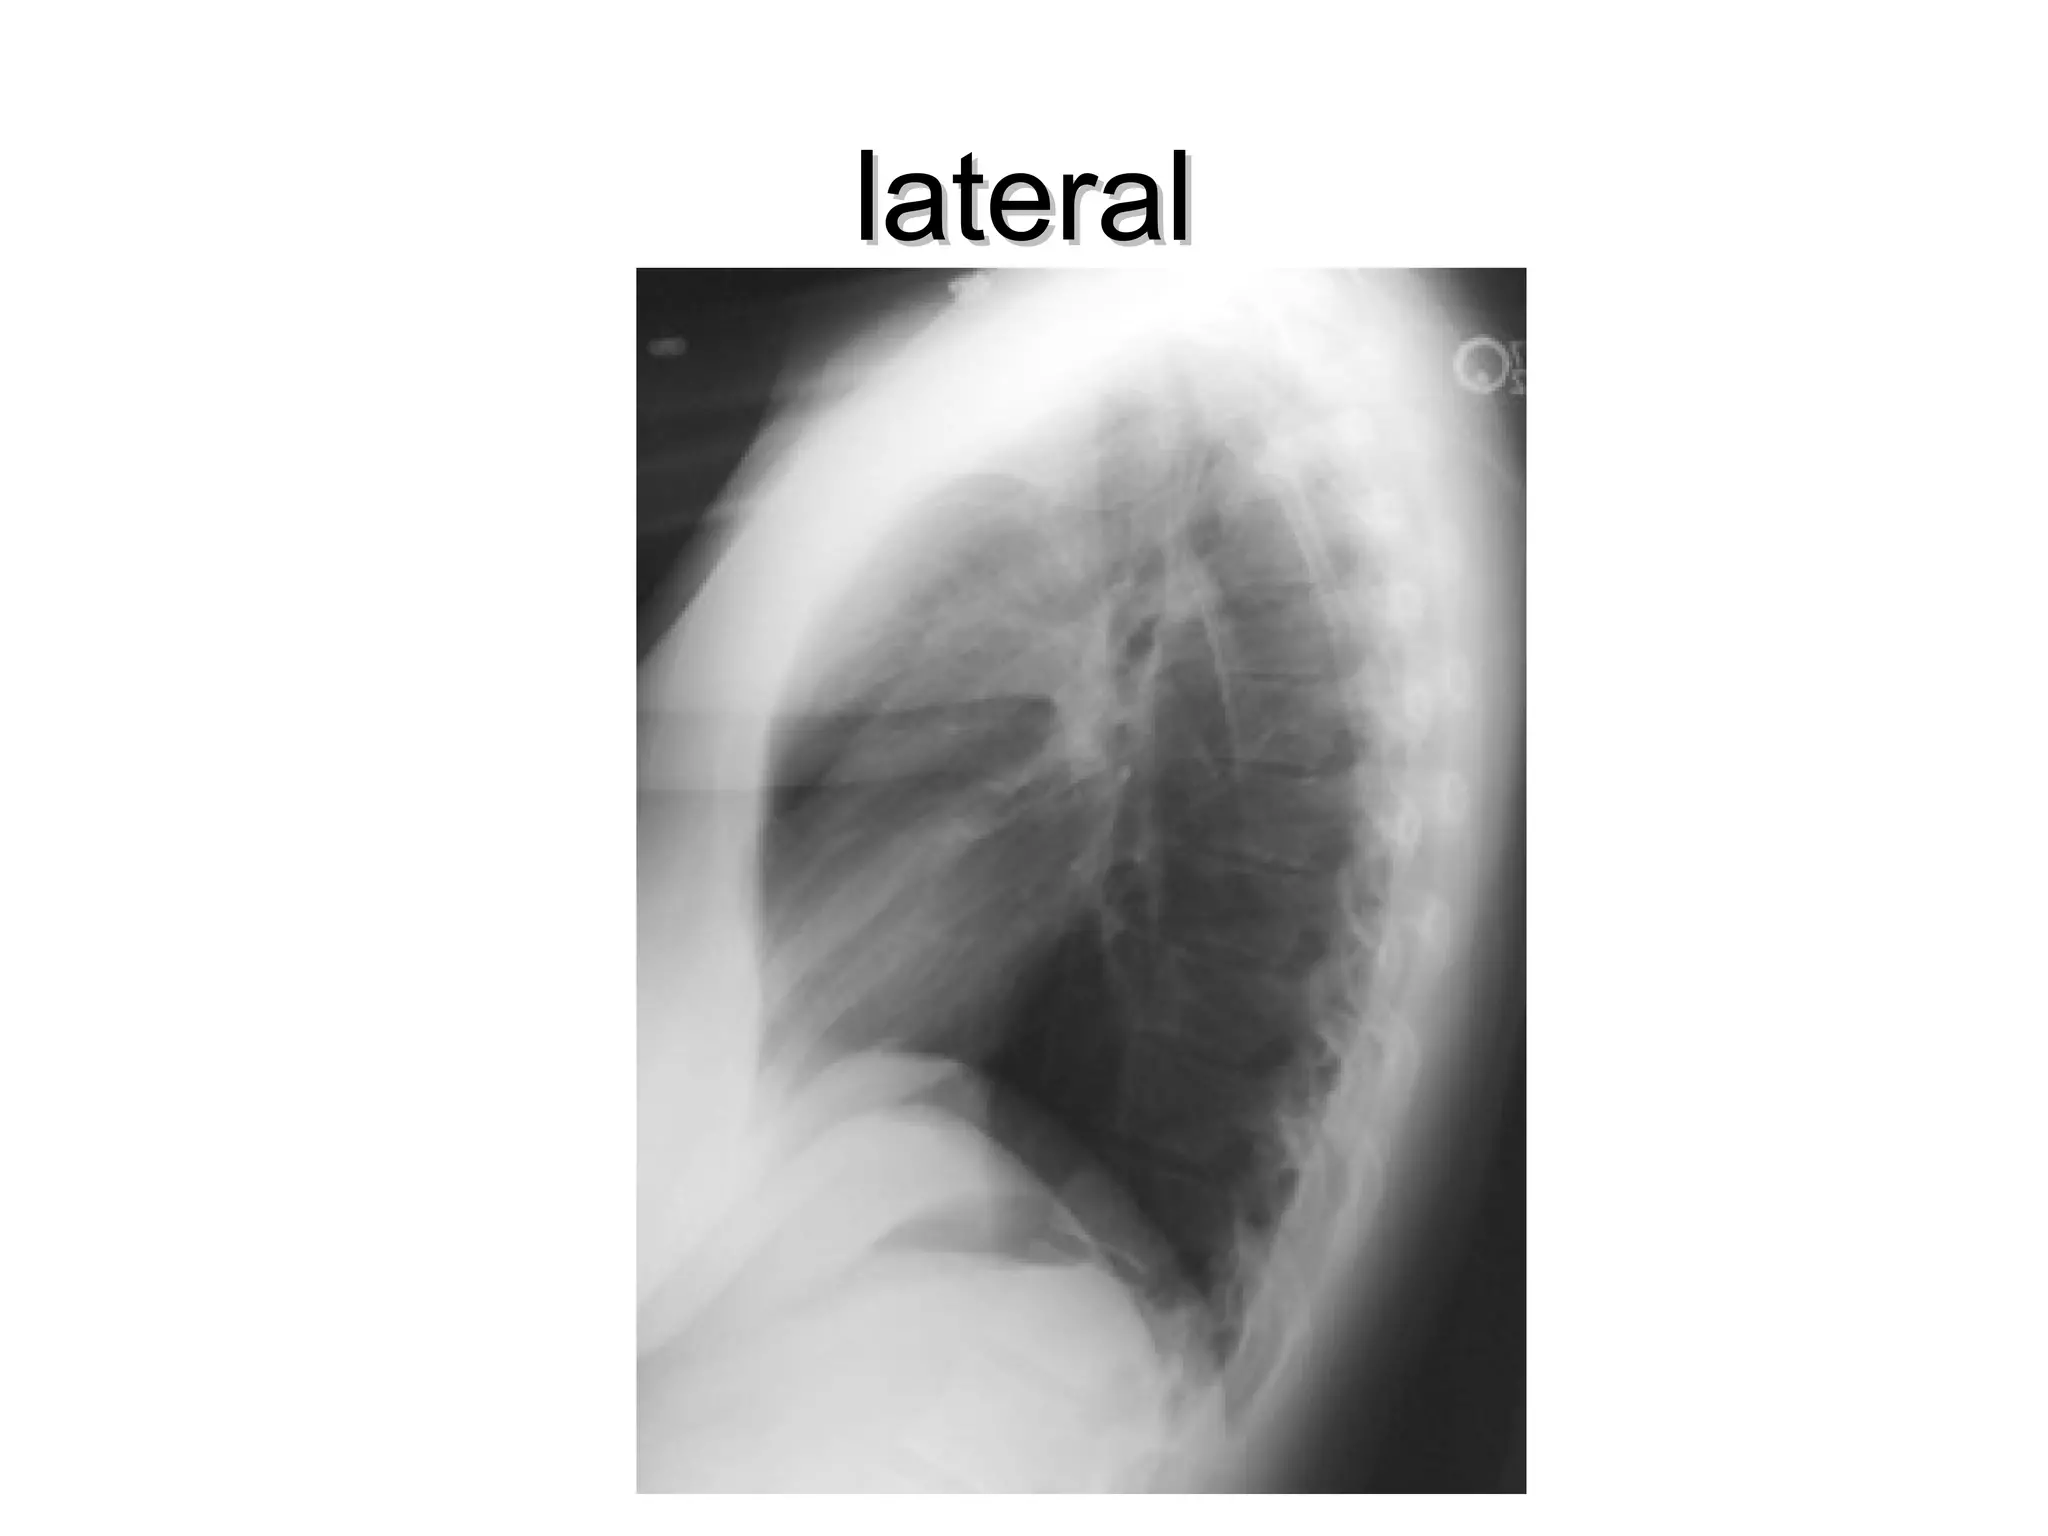

Viewing the lateral film

• Routinely the left side is adjacent to the

film

lateral